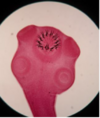

Hymenolepis nana scloex

48

Cysticercosis Infective vs diagnosic?

Infective stage: embryonated eggs Diagnostic stage: cysticercus (imaging,

Taenia solium Cysticercus cellulosae (larval stage)

66

Hymenolepis nana 4 suckers , short rostellum with a single row of hooklets (armed), thick neck Nana puckering for a kiss